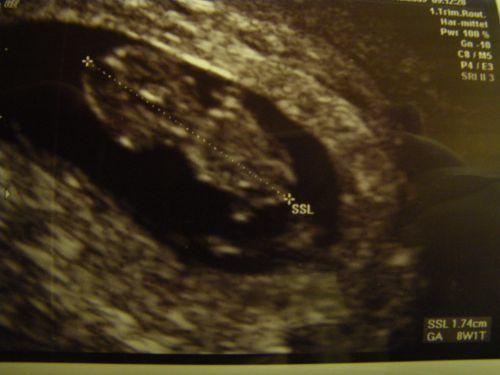

hallo, mir fällt ein riiiiiiiiesen stein vom herzen! dem baby gehts gut! es ist von kopf bis po 1,74 cm gross. das herzchen bubbert wie gehabt :-)... und ein hämatom in der gebärmutter ist auch nicht in sicht. blut muss also vom muttermund kommen :-) hab jetzt auch meinen Mu-Pass ausgefüllt bekommen und meinen Termin ausgerechnet bekommen. ist jetzt defintiv der 15. juli :-) lg

Bild zu zurück vom arzt :-) - Forum für Juli - Mamis